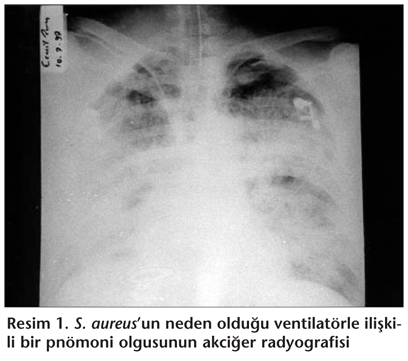

Ventilatörle ilişkili pnömonide radyolojik inceleme çok değerlidir fakat özellikle ventilatör tedavisi alan hastalarda akciğerlerde infiltrasyona yol açan birçok infeksiyon dışı neden mevcuttur (Tablo 2) [13,16].

Ventilatörle ilişkili pnömonilerde mikrobiyolojik olarak en sık endotrakeal aspirat (ETA) örneği incelenir. Korunmuş fırça yöntemi (KF) ve bronkoalveolar lavaj (BAL) gibi bronkoskopik yöntem ile alınan örnekler ventilatörle ilişkili pnömoni tanısında daha yardımcıdır. Tüm bu örnekler kantitatif kültür ile değerlendirilmelidir. Bronkoskopik yöntemler, endotrakeal aspirat yönteminden daha üstün olmakla birlikte, bunların rutin kullanımı konusunda fikir birliği yoktur. Bronkoskopik yöntemlerin daha invaziv ve pahalı olmaları önemli dezavantajlarıdır. Endotrakeal aspiratın kalitatif kültüründe mikroorganizma varlığı kolonizasyon veya infeksiyonu gösterir. Kantitatif kültüründe 105 cfu/mL ve üzerinde üreme olmasının mikrobiyolojik tanıda duyarlılığı %67-91 arasında, özgüllüğü ise %59-92 arasındadır. Endotrakeal aspiratın Gram boyama ile değerlendirilmesi ve kalitatif kültürü, pnömoni varlığında antibiyoterapiyi yönlendirebilir fakat özgüllüğünün düşük oluşu gözardı edilmemelidir. Önceden antibiyotik kullanımının yukarıda anlatılan yöntemlerin sonuçlarını etkileyebileceği unutulmamalıdır. Endotrakeal aspiratın Gram yöntemiyle boyanan preparatında her alanda yassı epitel hücre (SEC) sayısının 10’un üzerinde ve polimorf nüveli lökosit (PNL) sayısının 25’in altında olması alınan örneğin uygunsuzluğu açısından değerli bir kriterdir. Pnömoni düşünülen hastada mutlaka kan kültürü alınmalıdır(Resim 1, Resim 2) [13,17-20].